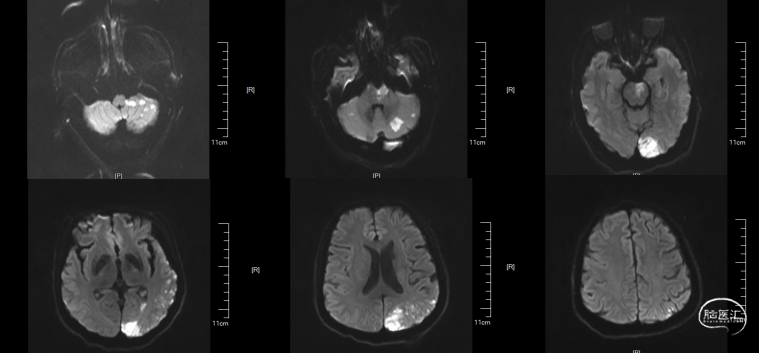

术后DWI